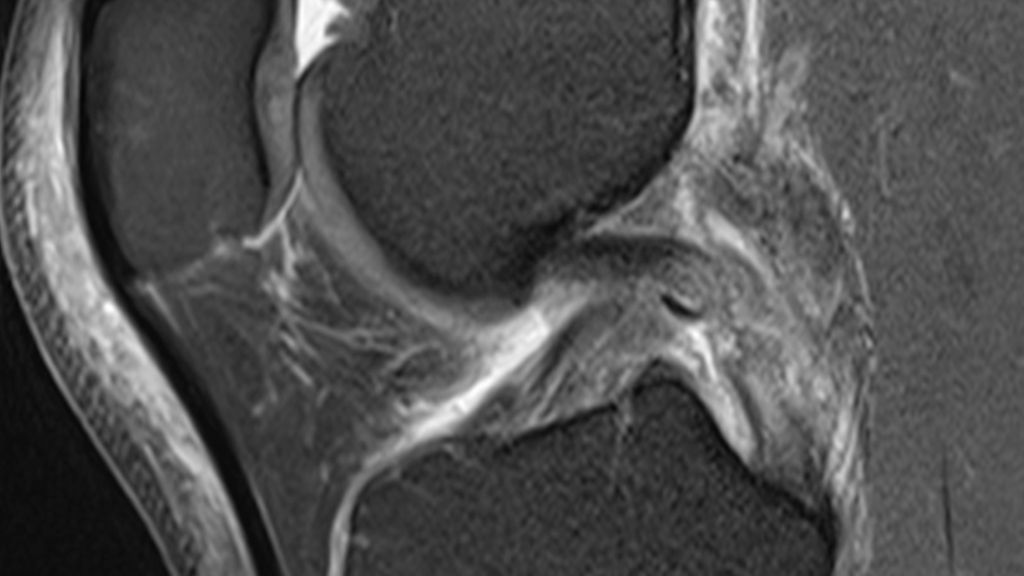

Abb. 1–5: Fallbeispiel: Patient 40 J., männlich, Verletzung beim Fußball, Op 3 Wochen nach Verletzung. Hier gezeigt: 3 x MRT präoperativ sowie Röntgen postoperativ, a.p. und seitlich. Mediale Rekonstruktion nach LaPrade mit Tightropes, VKB-Plastik und HKB-Plastik „all-inside“

Magnetresonanztomografie (MRT): Das MRT ist das wichtigste Instrument zur Beurteilung des Ausmaßes der ligamentären Schädigungen, zur Identifikation begleitender Meniskus- und Knorpelläsionen sowie zur Erkennung ossärer Verletzungen. Porrino et al. (2019) betonen in ihrem Review die Bedeutung der präoperativen MRT, um für den Chirurgen relevante Informationen über Verletzungsmuster zu liefern.1